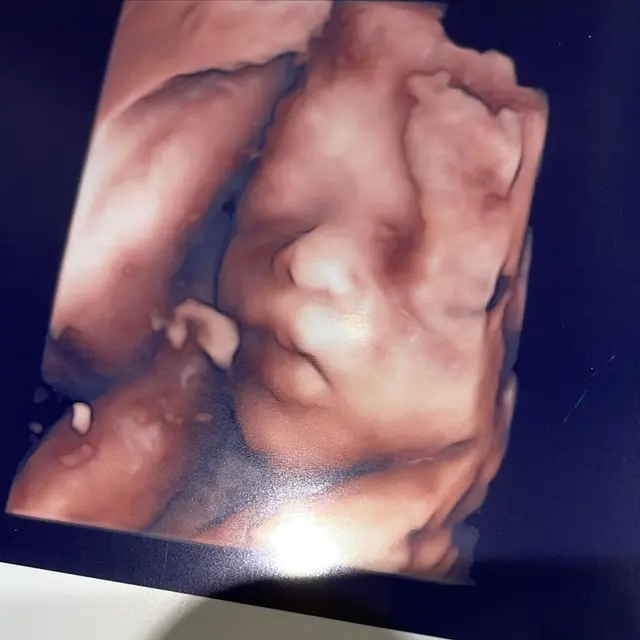

Kali ini, Nathalie Holscher memperlihatkan secara lebih dekat dan potret calon anaknya. Dalam foto tersebut terlihat jelas mata, hidung, hingga bibir anak Nathalie dan Sule ini.

Sedangkan dalam videonya terlihat calon anak Nathalie Holscher ini menggerakan bibirnya. "Duh duh bibirnya," ujar seorang yang suaranya ada di video tersebut.

Uniknya ada juga sederet warganet yang mengatakan jika buah hati Nathalie mirip dengan Sule. "Foto nomor dua mirip kang Sule bun," kata seorang warganet.